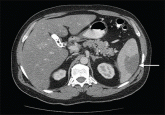

His symptoms and imaging findings suggested an infarction in the spleen, but what caused the infarction?

Corticosteroid treatment resulted in clinical improvement after 3 months.